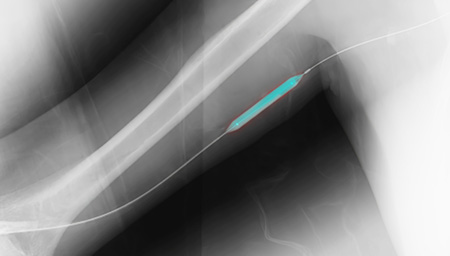

원하는 위치까지 카테터를 삽입

흉부 엑스레이로 카테터 위치 확인